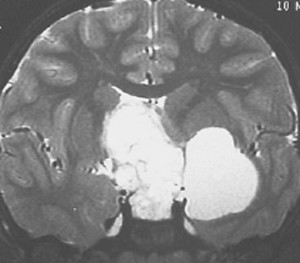

この子の症状は頭痛だけ。両親はなぜ気づかなかったのかと疑問を持ちますが,巨大になるまで症状が出ないこともあるのです。左のCTで腫瘍の周囲にバラバラと白い点状の石灰化があるので診断できます。左の視床下部から発生したクラニオでした。開頭手術しますが超高難易度です,怖いです (┯_┯) 複数回開頭手術になりましたが結果的に全摘出できています (by Dr 山本哲哉)。

危険な のう胞性 頭蓋咽頭腫 cystic craniopharyngioma

上に示した例は,巨大な「のう胞性」頭蓋咽頭腫でもあります。袋の中に液体が入っているのを「嚢胞 cyst」といいます。大部分は液体なので,袋を破れば腫瘍は簡単に小さくなります。